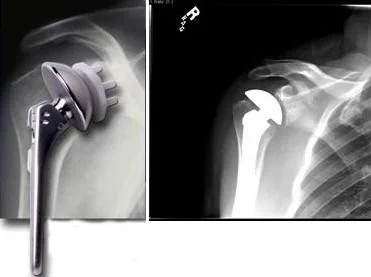

Arthroplasty

- Arthroplasty (joint replacement)